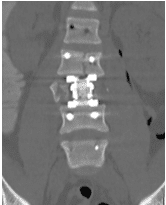

Patient was operated and the spinal canal cleaned up of all bony fragments. The spine was fixed from the side and the back to take care of instability.